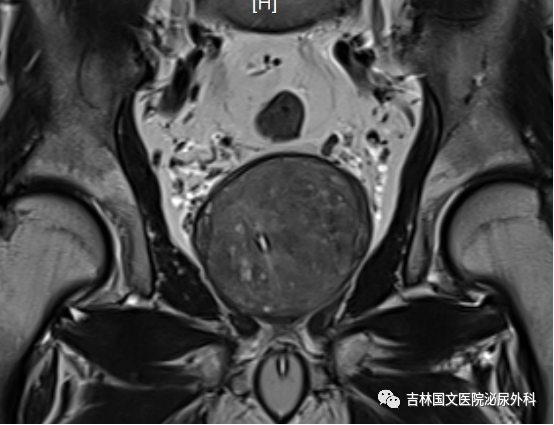

入院后行相關(guān)檢查,發(fā)現(xiàn)患者前列腺增生巨大,因治療延誤,已導(dǎo)致前列腺并發(fā)癥,出現(xiàn)膀胱功能受損,雙腎輕度積水。同時(shí)發(fā)現(xiàn)有腦梗死、雙肺支氣管炎、肺氣腫等基礎(chǔ)疾病,請(qǐng)相關(guān)科室會(huì)診,積極調(diào)整,改善身體素質(zhì)。同時(shí)明確向家屬告知手術(shù)風(fēng)險(xiǎn),手術(shù)后果,取得家屬支持認(rèn)可。家屬全力配合。經(jīng)認(rèn)真準(zhǔn)備,

患者在椎管內(nèi)麻醉下行經(jīng)尿道前列腺電切術(shù)。術(shù)中見前列腺中葉側(cè)葉明顯增大,向膀胱突出,尿道前列腺部明顯延長(zhǎng),因前列腺阻擋,膀胱加強(qiáng)收縮,膀胱壁明顯增厚,形成特有“小房小梁”結(jié)構(gòu)。在麻醉科精心配合下,谷欣權(quán)教授、張寶主任給予認(rèn)真細(xì)致手術(shù),術(shù)中反復(fù)止血,術(shù)后出血少,未輸血。術(shù)后認(rèn)真看護(hù),未出現(xiàn)腦梗死肢體功能障礙,未出現(xiàn)呼吸功能衰竭、心功能不全等常見并發(fā)癥。拔出尿管,患者排尿通暢,如開閘洪水,一瀉千里,老人露出久違笑容,家屬也非常開心,壓在心中的石頭終于落了地。